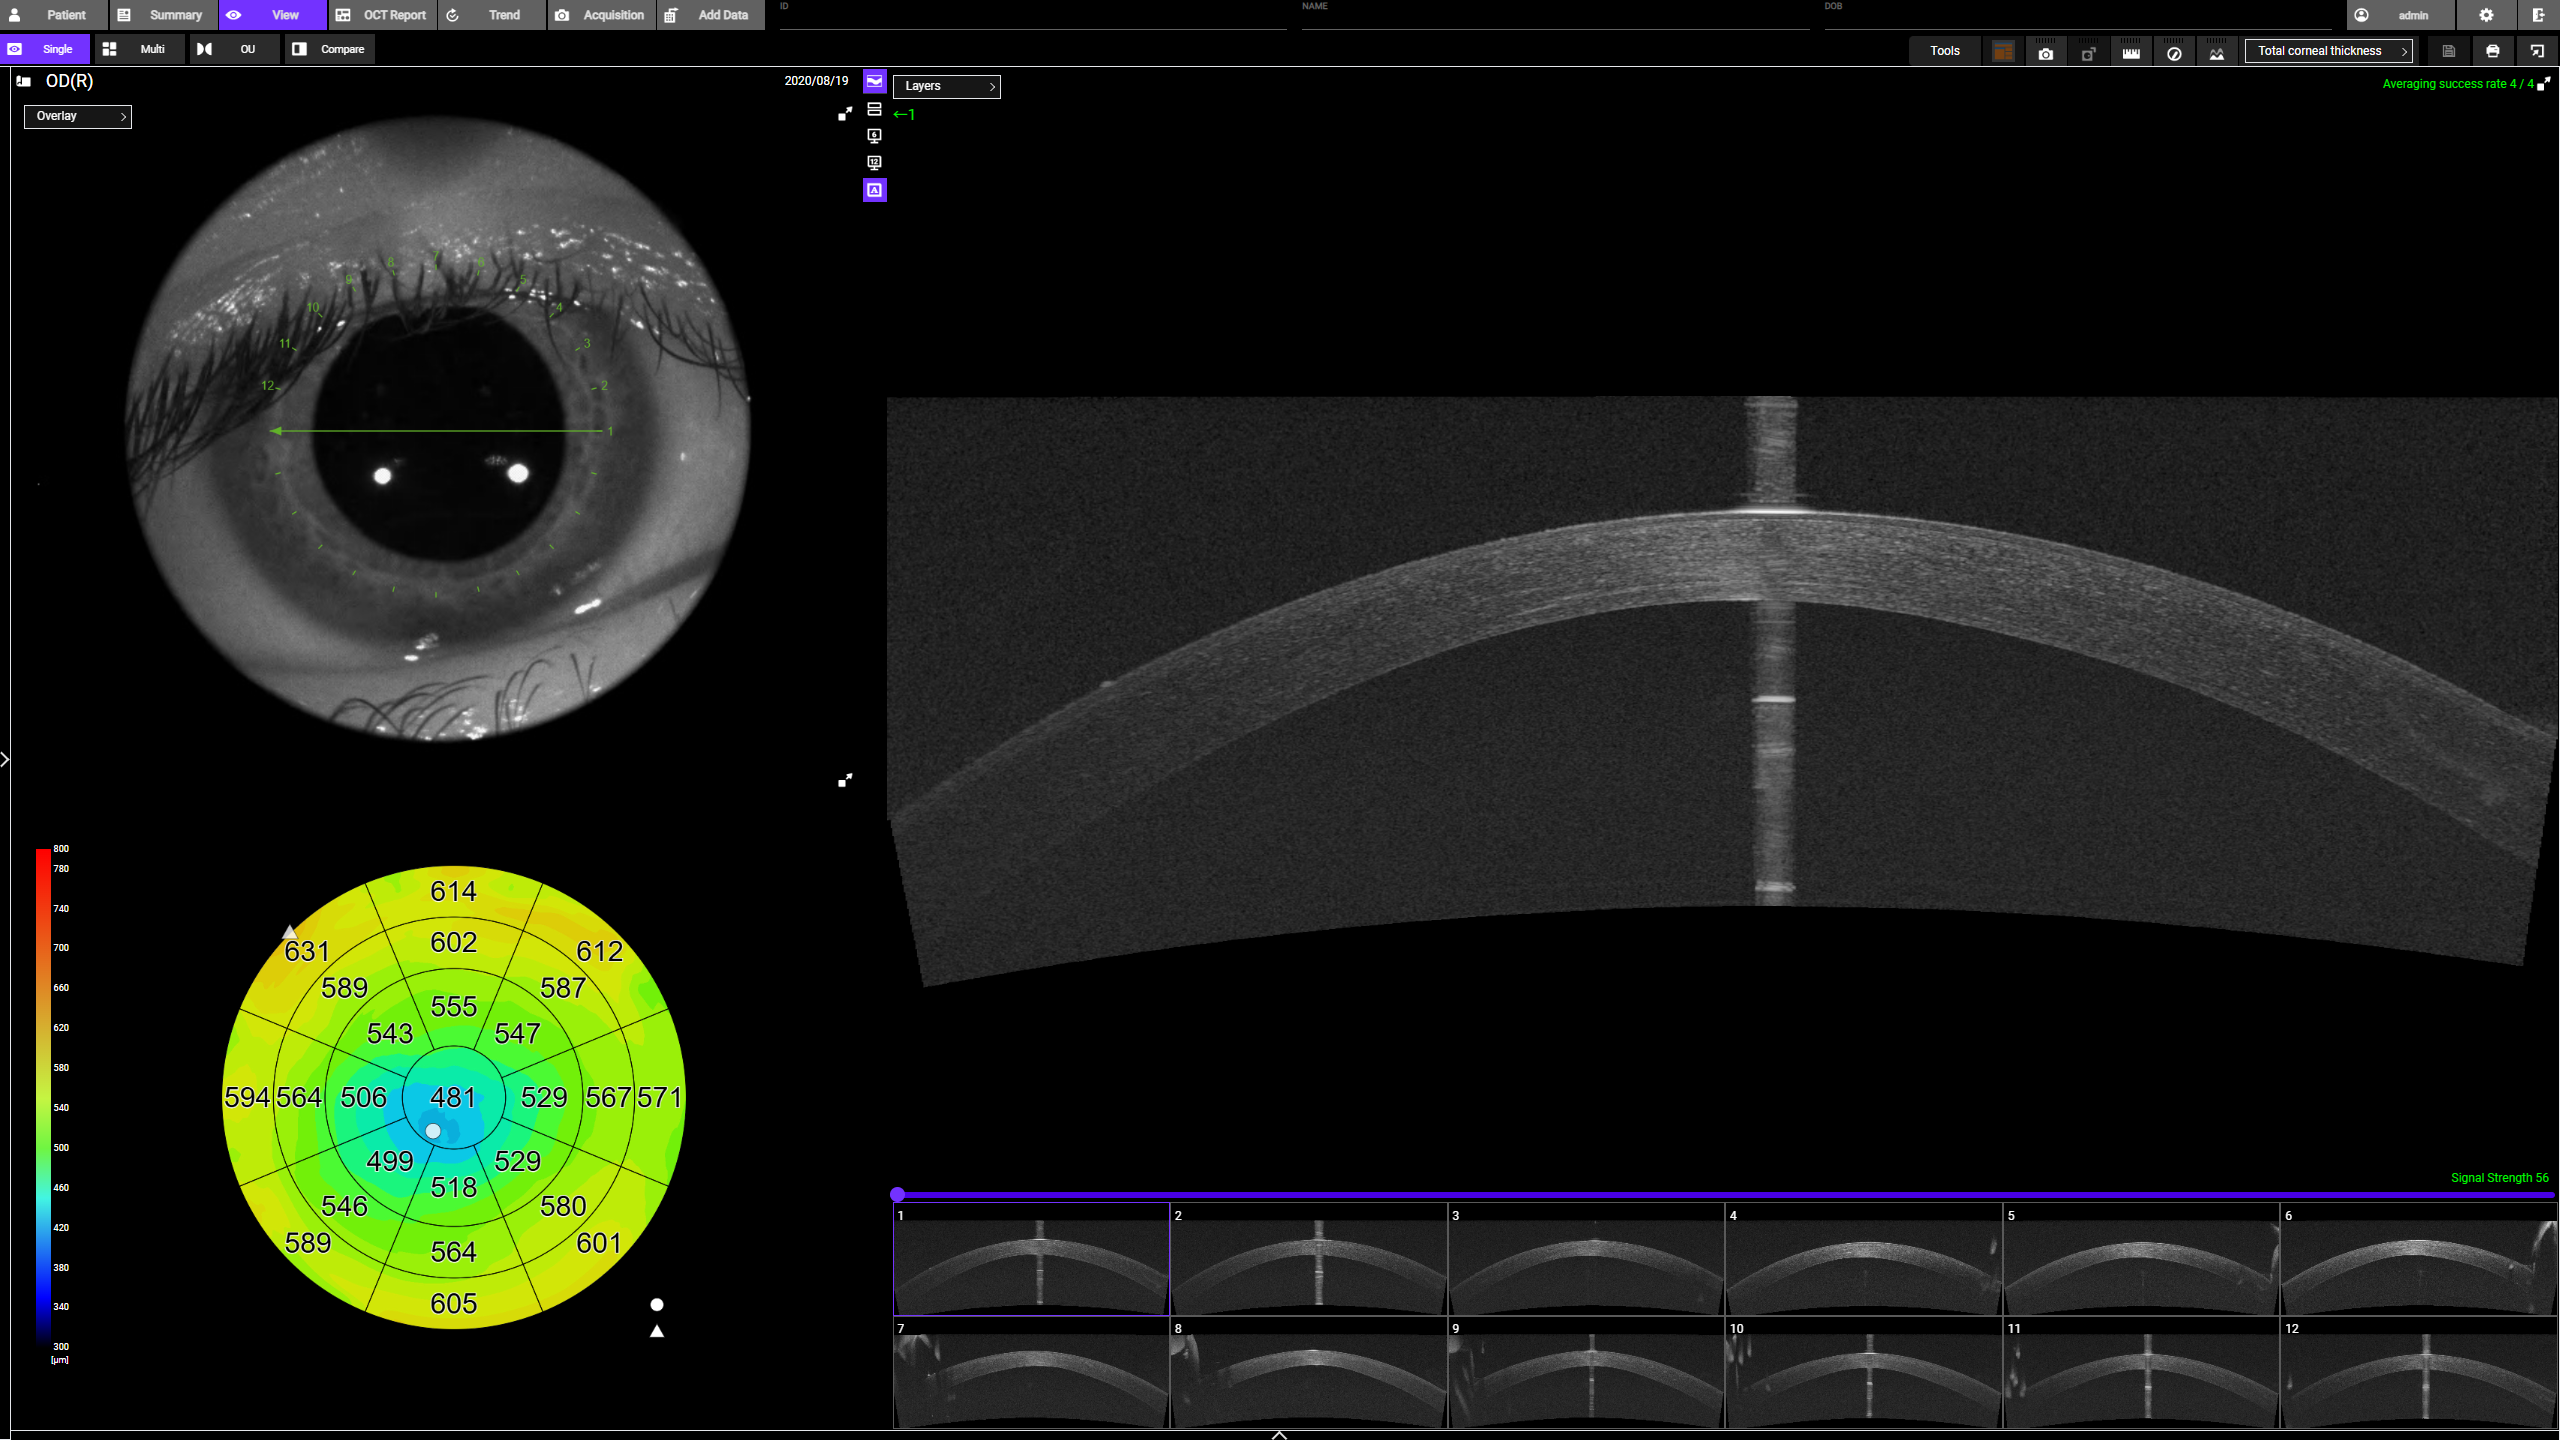

- Anterior Segment Analysefunktionen: Kammerwinkelmessung, Epithelium Mapping, Stroma Mapping

- Komplette Glaukom- und Vorderabschnitts-Analyse: 12×9 mm 3D Wide Scan für Sehnerv und Makula in einer Aufnahme; optionale Vorderabschnitts-Bildgebung für umfassende Diagnostik